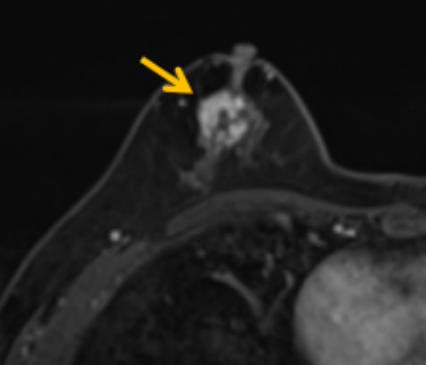

陳寶瑩評估圖像后發(fā)現(xiàn)病變?yōu)閮H僅在磁共振增強(qiáng)時(shí)顯示,為非腫塊樣病變,比較散,必須取得足夠多的組織才能確保病理檢查的準(zhǔn)確性,常用的核芯針活檢獲取的組織較少,因此最終確定了磁共振引導(dǎo)下行真空輔助抽吸旋切活檢。取得患者及家屬認(rèn)可后,陳寶瑩帶領(lǐng)團(tuán)隊(duì)開始進(jìn)行術(shù)前準(zhǔn)備。

針對患者乳房小固定難度大這一問題,陳寶瑩通過巧妙體位和固定器的調(diào)整,順利固定好乳房。經(jīng)過磁共振多模態(tài)掃描,陳寶瑩找出病變活性成分相對集中區(qū)域,精準(zhǔn)確定穿刺路徑,置入引導(dǎo)針、旋切針,到位后多角度旋切取出足量組織,拔除旋切針后即時(shí)行磁共振掃描,精準(zhǔn)取得組織且術(shù)區(qū)出血很少,遂加壓包扎,整個過程非常順利,旋切活檢后患者回家休息。兩天后隨訪,李女士沒有任何不適,五天后皮膚上幾毫米的小切口已經(jīng)愈合。最終病理結(jié)果證實(shí)為乳腺導(dǎo)管原位癌,為早期乳腺癌,為患者后續(xù)針對性治療奠定了基礎(chǔ)。